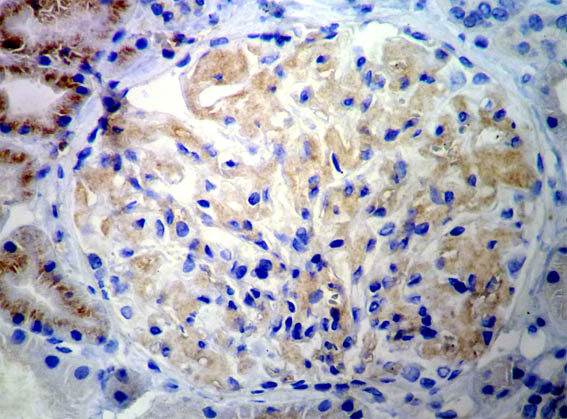

Figure 8.

Immunostaining for kappa light chains, X400.

Figure 9.

Immunostaining for lambda light chains, X400.